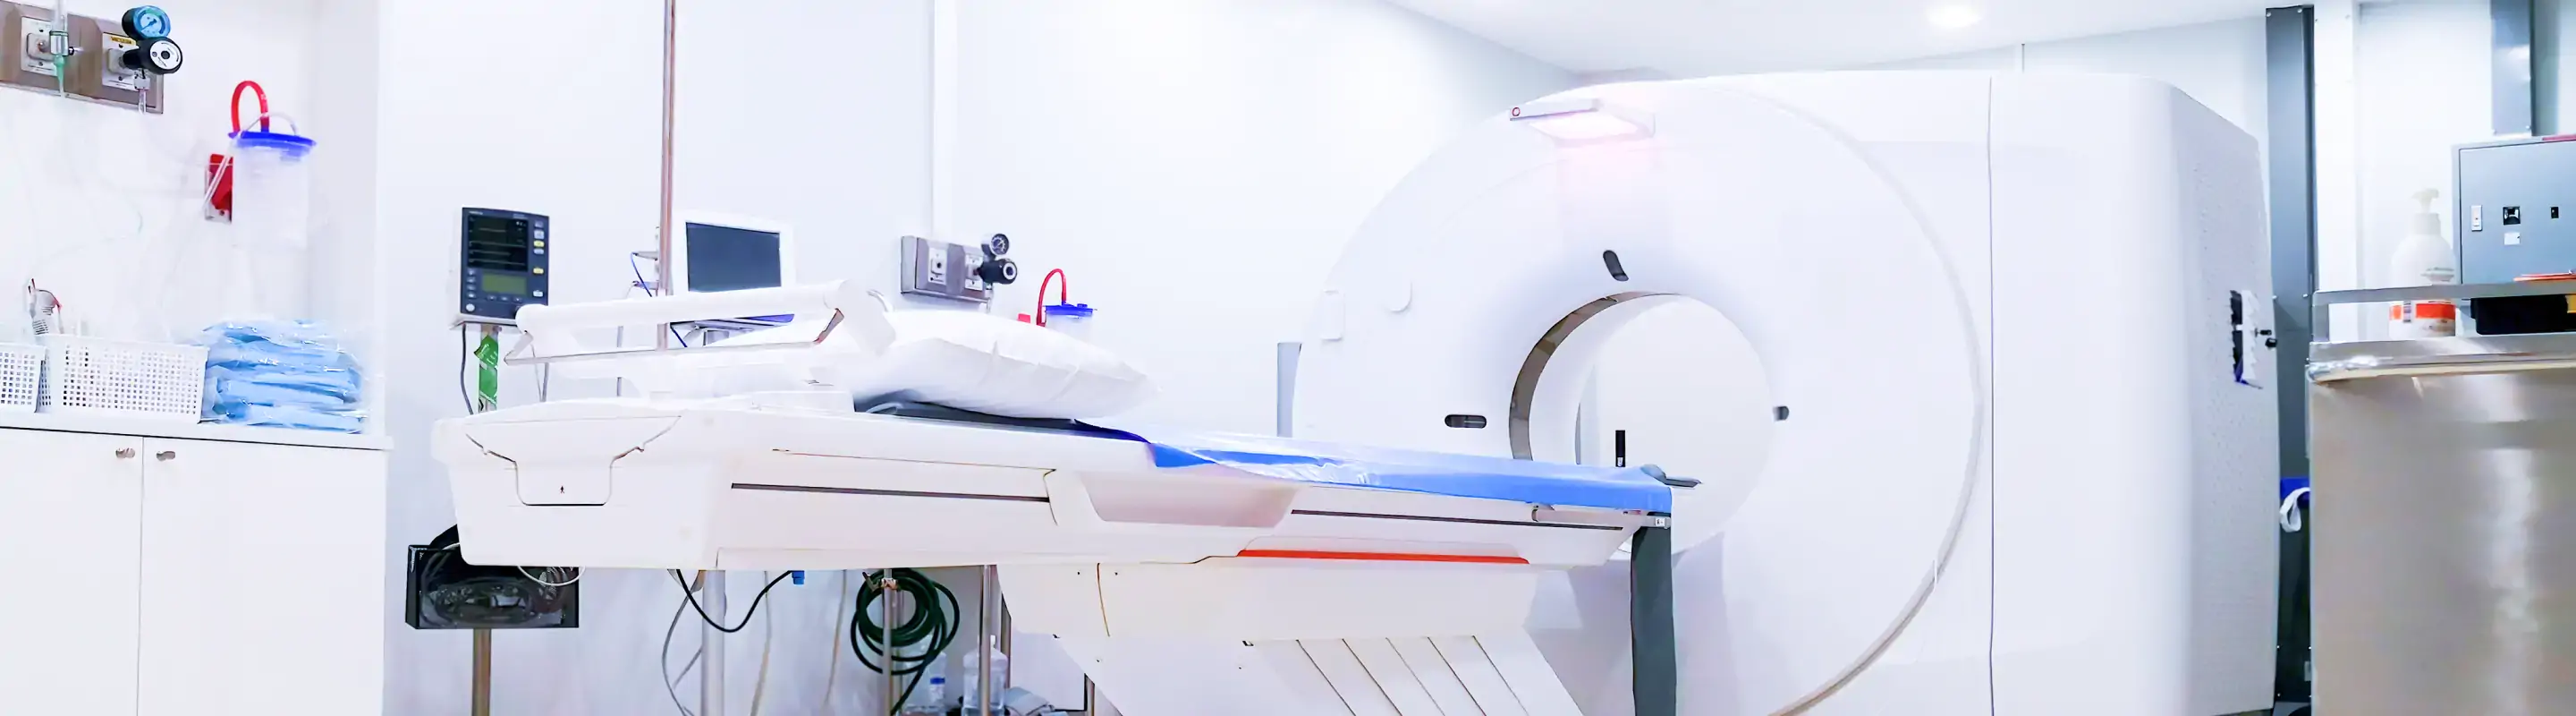

正確な診断にはMRIが必要です

レントゲンだけでは骨の形状しか確認できず、椎間板の変性・神経の圧迫程度・骨折の詳細は評価できません。当院では院内のMRIで脊椎・脊髄の状態を詳細に確認し、症状と合わせた専門的な診断を行います。「レントゲンで異常なしと言われたが症状が続く」という方も、ぜひご相談ください。